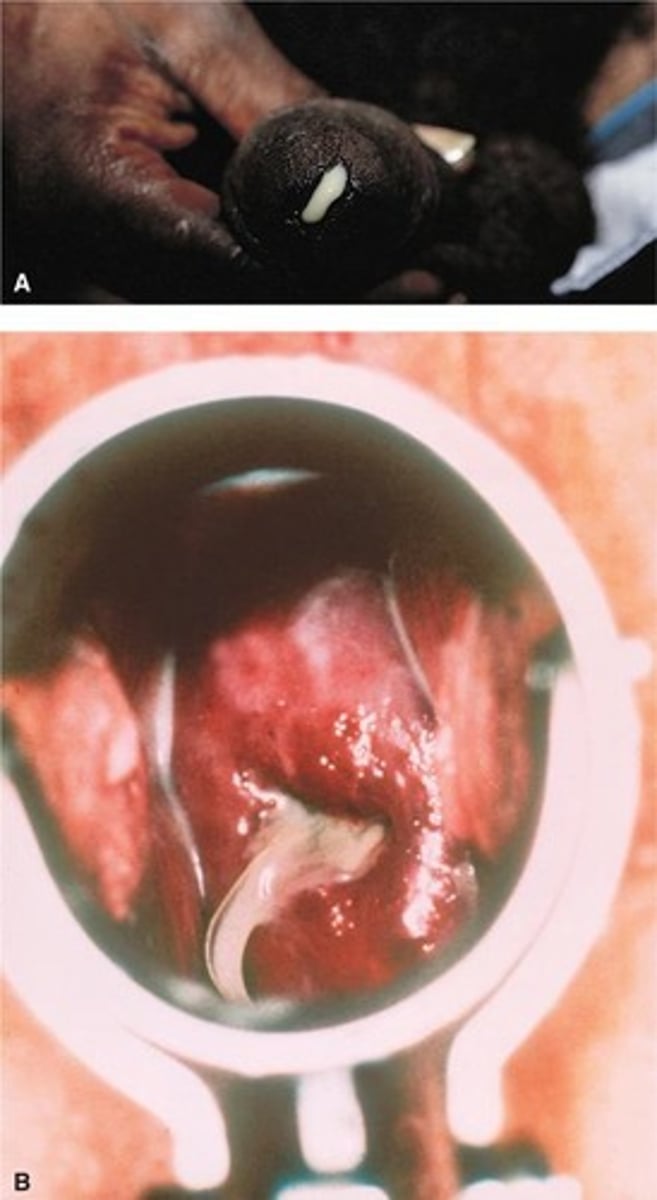

Chancre

Painless ulcer in primary syphilis stage.

Fluid-filled blisters from genital herpes outbreak.

Painless clusters of growths on genitals.

Vinegar Test